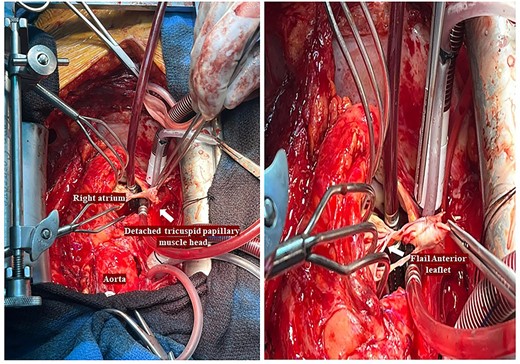

He had a redo-median sternotomy. Cardiopulmonary bypass was instituted through aortic cannulation connected to the bypass machine via a bifurcated arterial line along with the femoral ECMO cannula. The SVC and IVC were cannulated before opening the right atrium. The TV was inspected which revealed a flail anterior leaflet, attached to the ruptured head of the papillary muscle (Fig. 3).

Intraoperative pictures demonstrating a flail anterior leaflet attached to the ruptured head of the papillary muscle.

The leaflet was excised and a 27 mm Mitral Magna Ease tissue valve was implanted. He was successfully weaned off cardiopulmonary bypass and decannulated off ECMO in sinus rhythm. Post-operative ECHO showed a well seated and functioning TV prosthesis (Fig. 4).